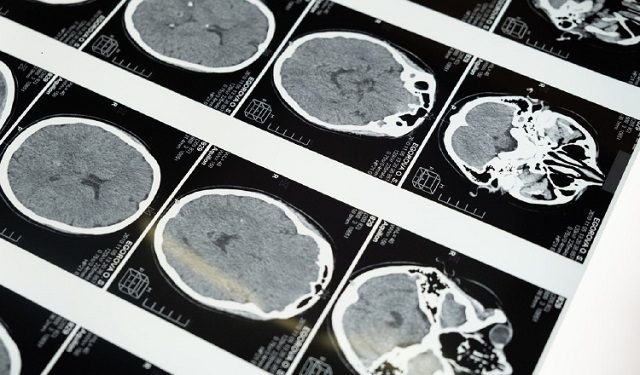

Los tumores del tronco encefálico pueden provocar la pérdida del equilibrio o movimientos torpes. Foto: Ilustrativa / Pexels